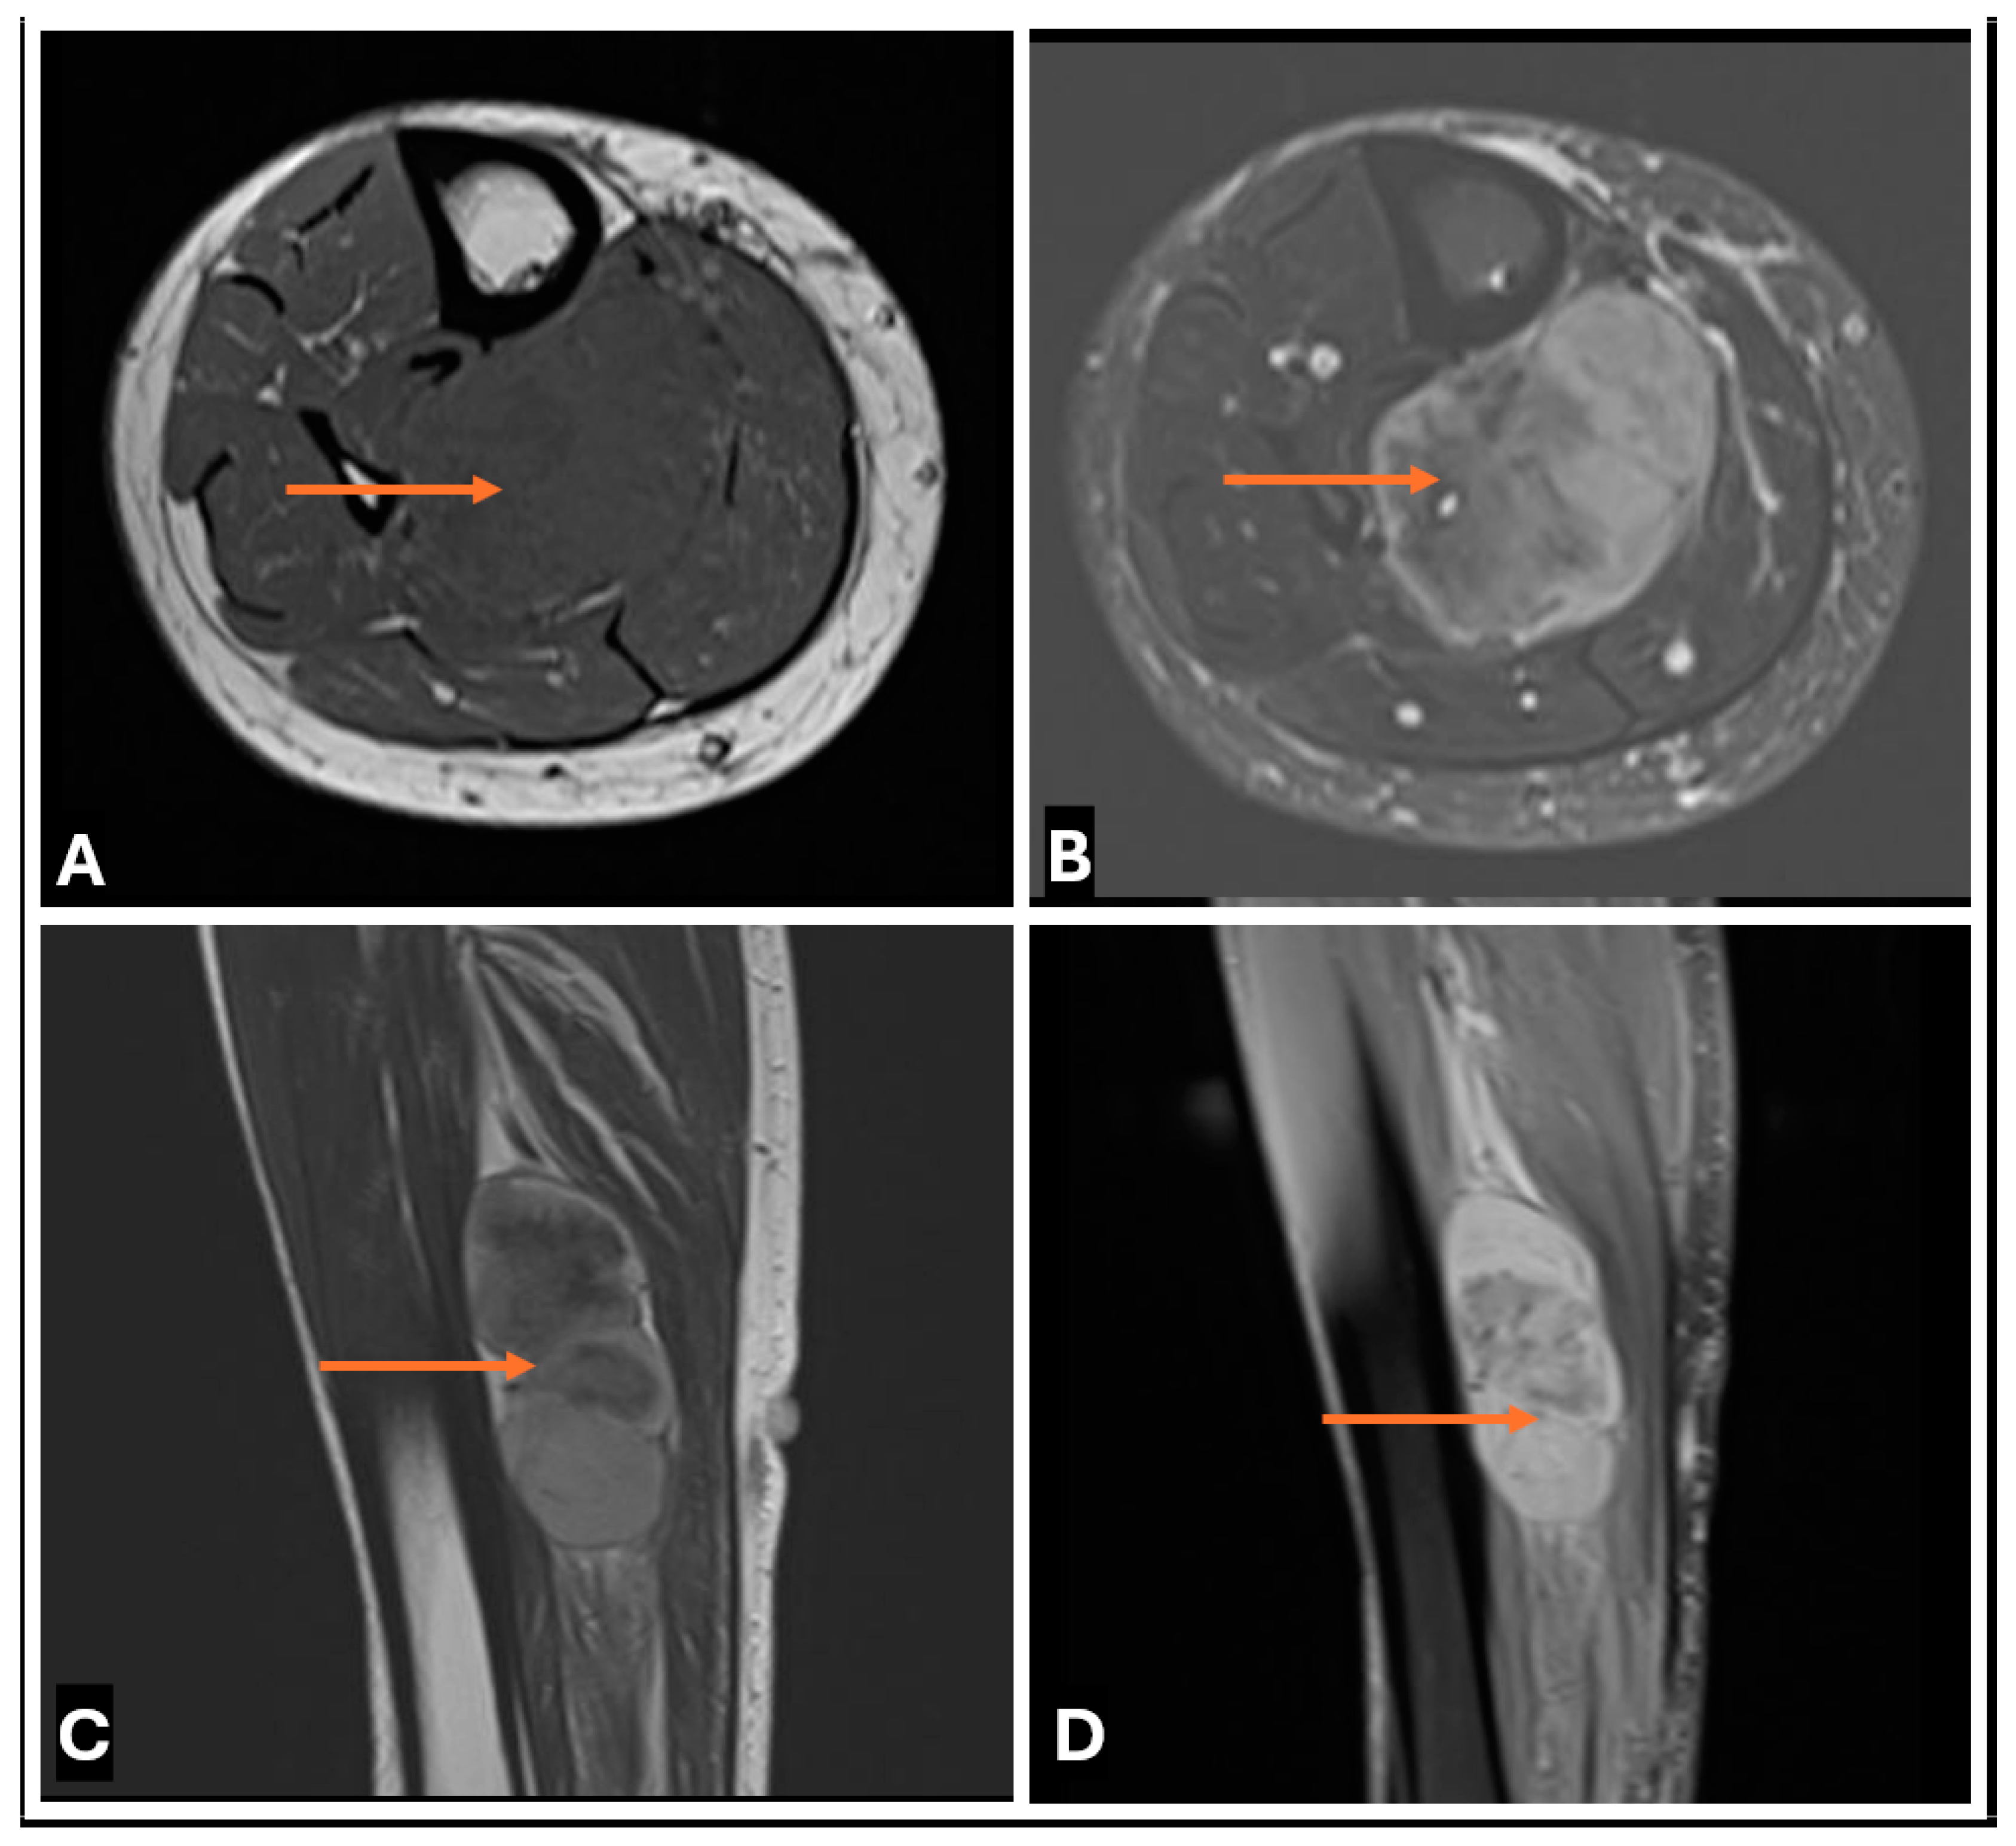

- Primary Sarcomas: Soft-tissue sarcomas are uncommon, accounting for just over 1% of adult malignancies. Synovial sarcoma, clear cell sarcoma, and epithelioid sarcomas are known to involve peripheral nerves. CT/MR reveals a large soft tissue mass with areas of necrosis or calcification and heterogeneous contrast enhancement. F-18 FDG uptake is useful for both tumor staging and treatment assessment (Figure 26, Figure 27 and Figure 28).